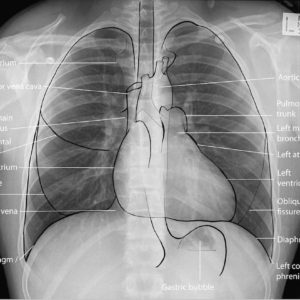

ފުއްޕާމޭ މައިގަނޑު ގޮތެއް ގައި އެކުލެވިގެން ވަނީ އިސްޕަންޖު ގަނޑެއް ފަދަ ދެގުނަވަނަކުންނެވެ. މިގުނަވަން ހިމެނެނީ މޭގެ ދެފަރާތުގައެވެ. ކަނާތްފަރާތު ފުއްޕާމޭބެހިގެން ވަނީ 3 ބަޔަކަށެވެ (3 ލޯބްސް އަށެވެ). އަދި ވާތް ފަރާތު ފުއްޕާމޭ ބެހިގެން ވަނީ 2 ލޯބަށެވެ. ވާތް ފަރާތުޕުއްޕާމޭ ކަނާތްފަރާތަށް ވުރެ ކުޑަވާނެއެވެ. ސަބަބަކީ މޭގެ ވާތްފަރާތުގައި ހިތް އެކުލެވިގެން ވާތީ އެވެ.

ނޭވާލާއިރު، އަނގައިން ނޫނީ ނޭފަތުން ވައި ދަތުރުކުރާނީ ނޭވާ ހިނގާ ހޮޅި(ވައި ނޮޅިން) ގޮސް ޕުއްޕާމެއަށެވެ. ފުއްޕާމެއަށް ވަންނަވަރަކަށް މި ހޮޅި އިތުރުބައި ތަކަށް ބެހިގެންދެއެވެ. މިނިޒާމުގެ އެންމެ ކުދި ހޮޅި އަށް “ބްރޮންކިއޯލް” ގެނަމުން ނަންދެވިފާ ވެއެވެ. މިފަދަ ބްރޮންކިއޯލް ނިމޭހިސާބުގައި ނާޒުކުފަށަލައެއް ލެވިފައި ވާ ކުދި، ތުނި ކޮތަޅެއް ފަދަ ވަސީލަތެއް ހިމެނެއެވެ(އެލްވިއޮލައި).

މި އެލްވިއޮލައި ގެ މައިގަނޑު މަސައްކަތަކީ ނޭވައިން ގެނެސް ދިންވައިގައި ހިމެނޭ އޮކްސިޖަން ލޭގެތެރެއަށް ވާސިލް ކޮށްދީ، އަދި ހަށިގަނޑުގައި ބޭނުން ކުރެވި ތަގައްޔަރުވެފައި ވާ “ކާބަންޑައި އޮކްސައިޑް”ހަށިގަނޑުން ބޭރަށް، ނޭވާ ބޭރަށް ލާ ވަޔާއެކު ބޭރުކޮށް ލުމެވެ.

މިސަބަބަށް ޓަކައި ފުއްޕާމޭގެ މައިގަނޑު މަސައްކަތަކީ، އޮކްސިޖަން ހަށިގަނޑުގެ އެތެރެކުރުމާ ކާބަންޑައި އޮކްސައިޑް ގޭސް ބޭރުކުރުމެވެ. މިނޫނަސް ފުއްޕާމެއިން ހަށިގަނޑުގެ އެތެރޭގައި، ފުރާނަޔަށް މުހިއްމު، މާއްދާތައް އެއްހަަމައެއްގައި ބަހެއްޓުމުގައި ވަރަށް މުހިއްމު ދައުރެއް ކުޅެއެވެ.

ފުއްޕާމޭގެ ކެންސަރު އާންމުކޮށް ފަށަނީ ވައިނޮޅިޔާ، ކުދި ހޮޅިތަކާ އަދި އަލްވިއޮލައި ގެ އެތެރެފަށަލައިގެ ހިމެނޭ ސެލްތަކުން ނެވެ.